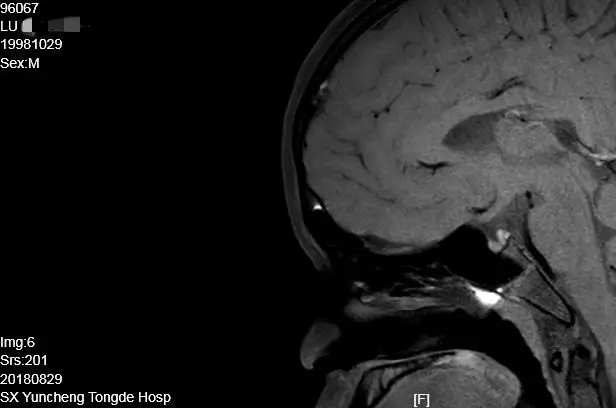

患者芦某,住院号96067

简要病史:男,19岁,在读大学生,以“生长发育缓慢16年”入院。身高144cm,智力正常,嗅觉正常,无多尿。小阴茎,睾丸容积2mL,无阴毛。

辅助检查:性腺六项:FSH 2.79 mIU/mL、LH 1.57 mIU/mL、PRL 269.7 uIU/mL、E2 5.0 pg/mL、P 0.91 nmol/L、T 0.36 nmol/L。生长激素轴:IGF-1 64.537ng/mL、IGFBP-3 1.9 ug/mL。甲状腺轴:FT3 5.0 pmol/L、FT4 17.81 pmol/L、TSH 4.89 uIU/mL。肾上腺皮质轴:皮质醇(8am)604.2 nmol/L。左旋多巴联合精氨酸生长激素激发试验:0分钟0.107 ug/L、30分钟0.07 ug/L、60分钟0.49ug/L、90分钟0.22ug/L。因患方原因未完成GnRH激发试验和HCG激发试验及染色体分析。骨龄测定:13.8岁。骨密度:z值-4.9,垂体MRI:腺垂体发育正常、垂体柄显示不清、神经垂体异位到漏斗干与漏斗突结合部。

病例特点:青年男性,嗅觉正常,无多尿。身材矮小,无第二性征发育,骨质疏松。性腺轴未启动,生长激素轴功能减退,肾上腺皮质轴和甲状腺轴正常。神经垂体异位,垂体柄消失。

最后诊断:1.异位神经垂体垂体柄阻断综合征;2.低促性腺激素性性腺功能减退症(HH);3.垂体性矮小症。

治疗方案:1.性腺轴:绒促素、尿促素序贯治疗;2.生长激素轴:重组人生长激素治疗。半年后随访,外生殖器等男性第二性征明显发育,身高增长6cm,骨密度显示骨矿化显著改善。